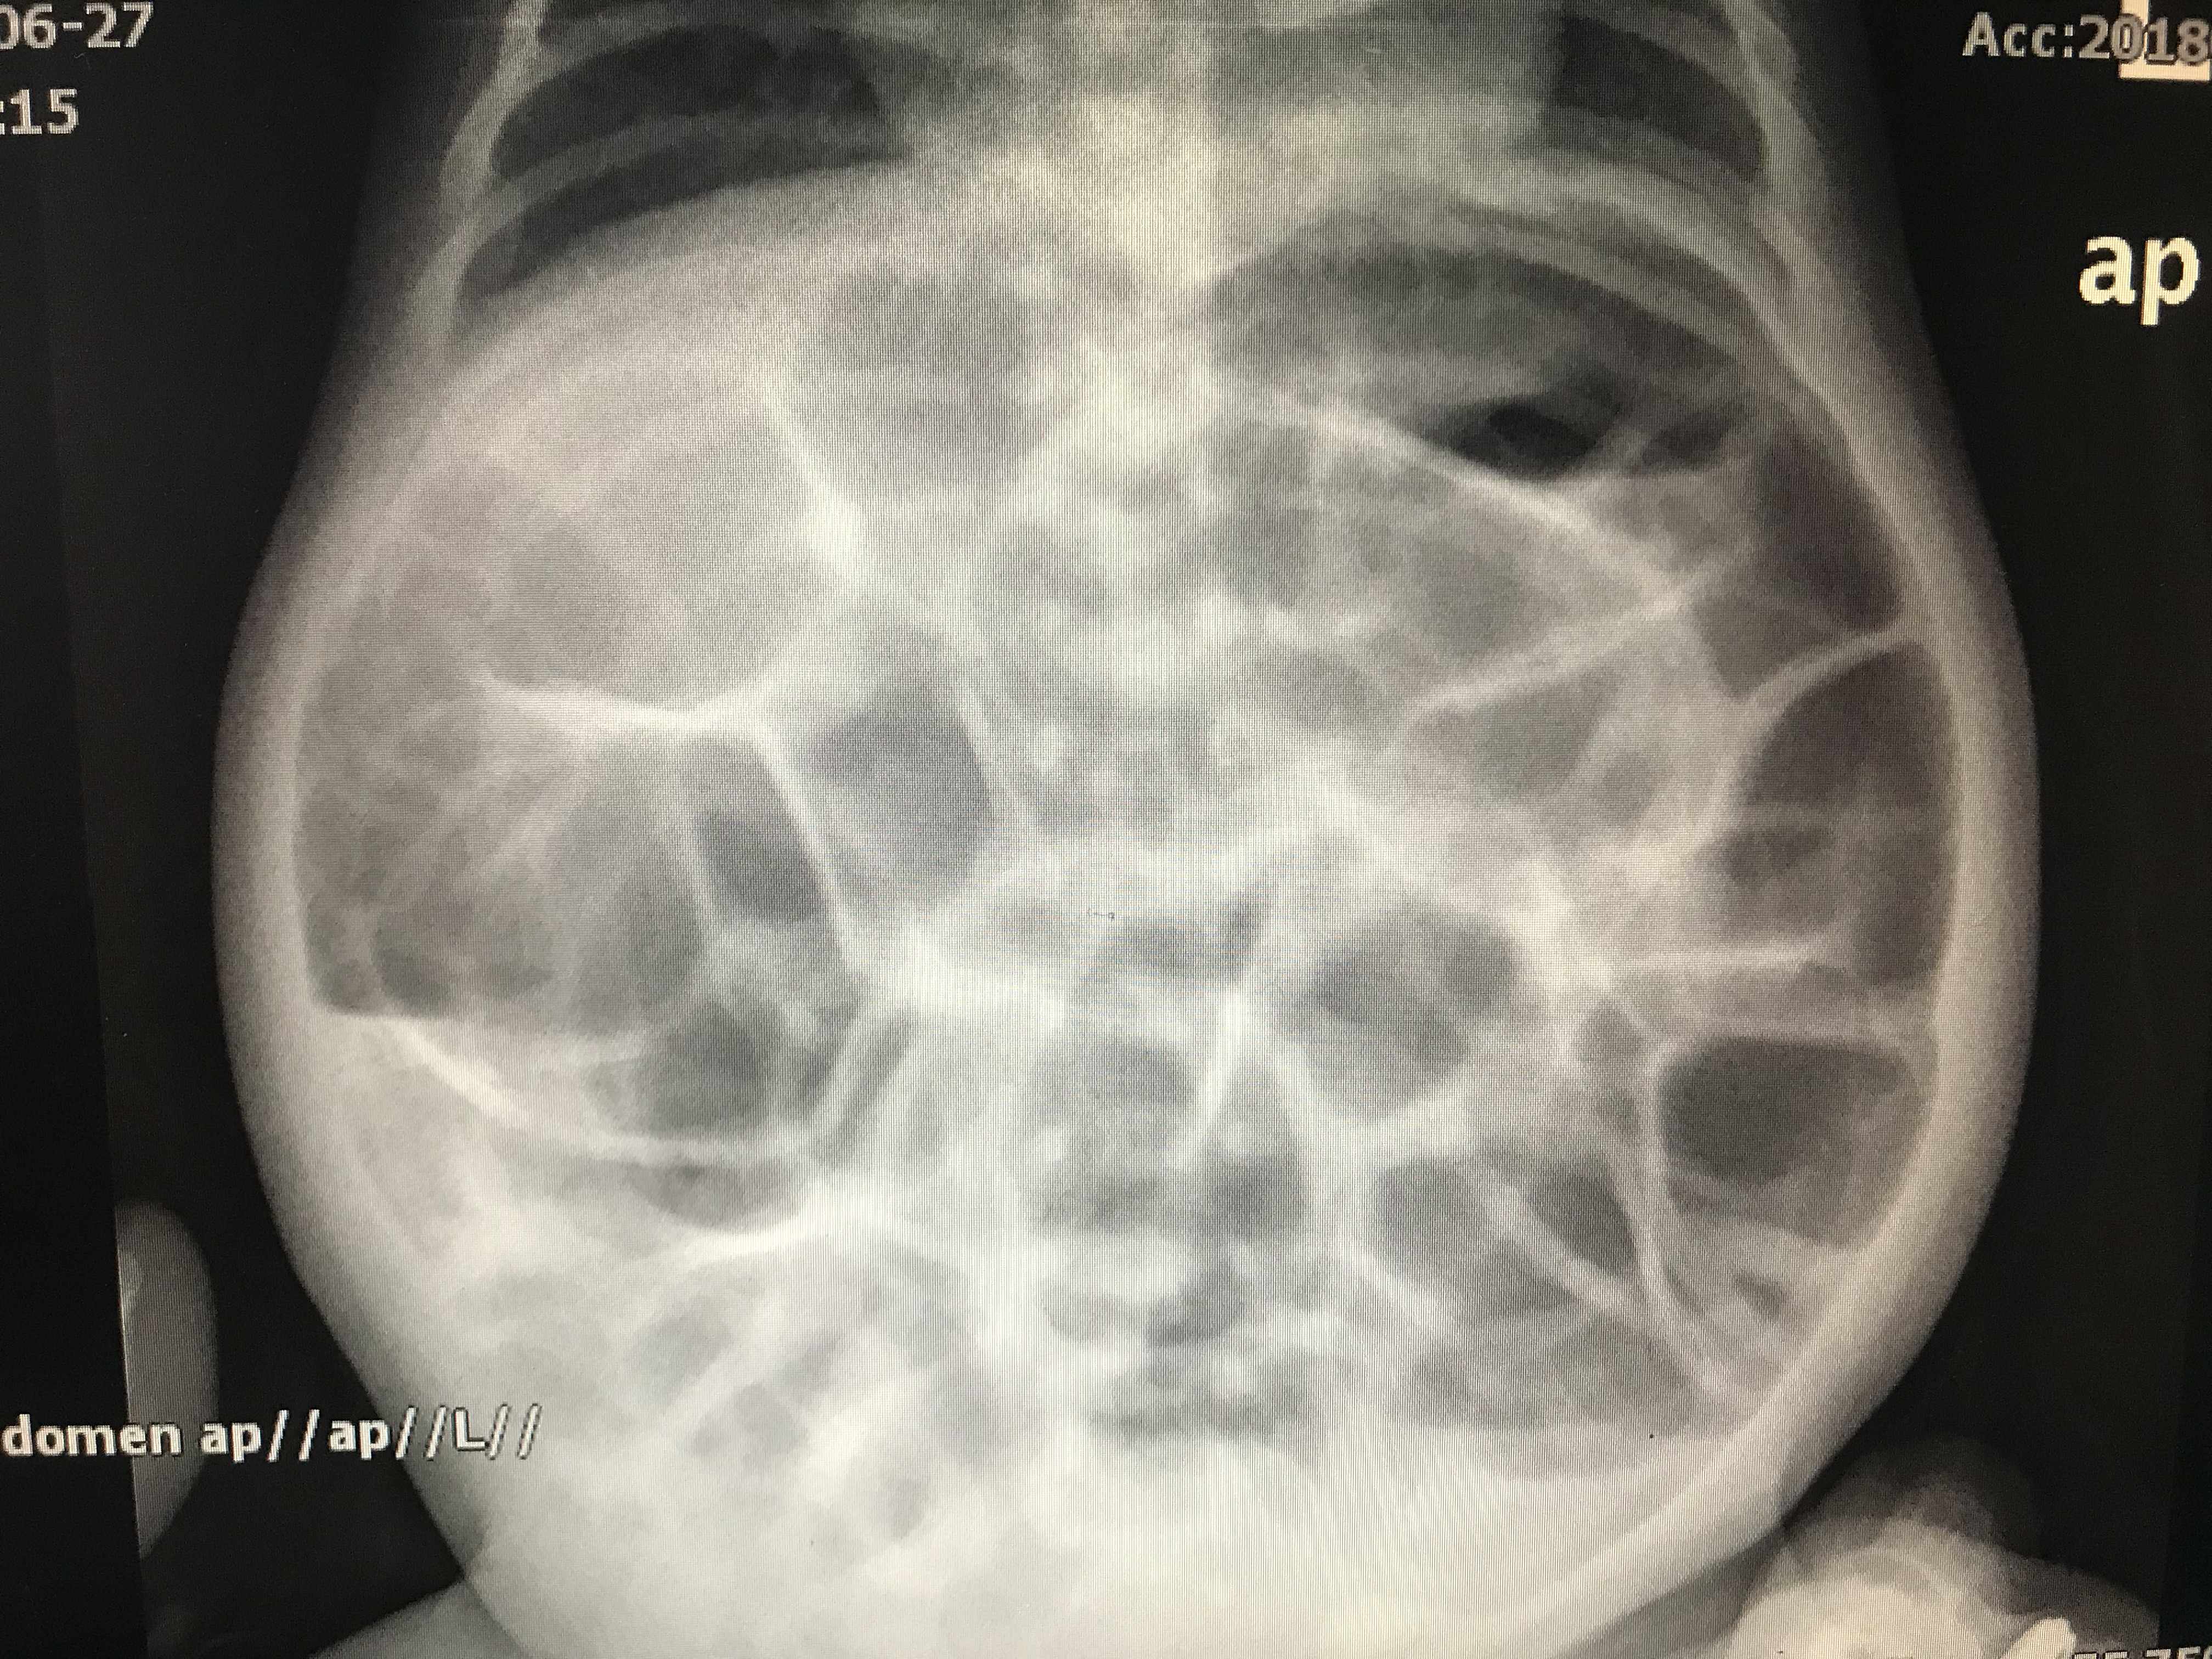

前2天,科室收了个33天的小宝宝,腹泻20多天,腹胀如鼓,甚至快压迫宝宝肺了,去了儿童医院考虑小肠结肠炎可能,需要住院治疗,当时没有床位,建议回到当地治疗。当时拍了腹部立位片如下图:全腹部胀气明显,左侧结肠肠管有扩张。是很担心早期小肠结肠炎,因为宝宝当时有早产病史。

全腹部胀气明显,左侧结肠肠管有扩张,外观似有僵硬。

腹壁静脉显露,可以看见肠型

4、腹部平片:早期胀气,或者液平,肠管僵硬,肠管排列紊乱。